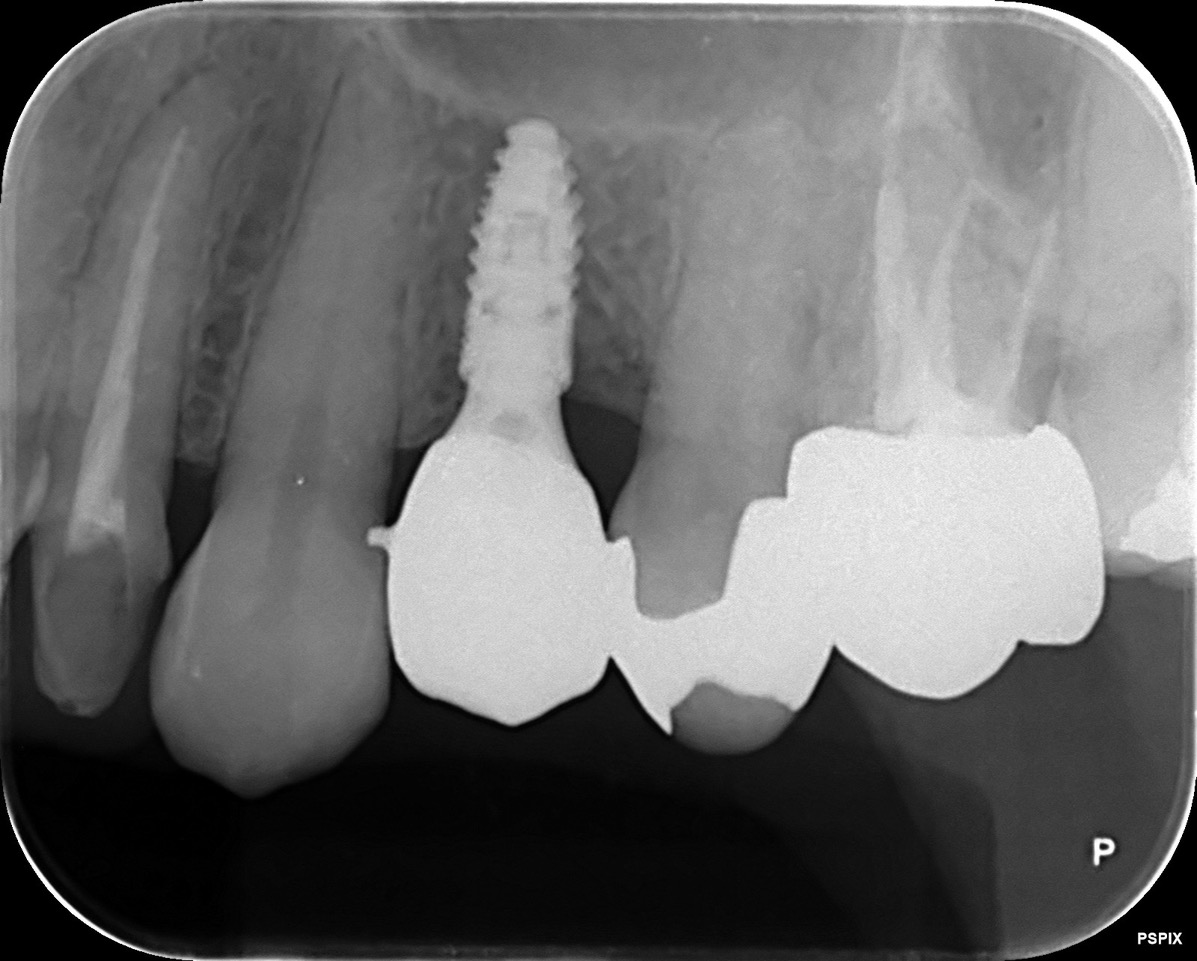

CASE 01

| 主訴 | 歯が割れた |

| 治療内容 | 左下6番 インプラント治療(骨の再生療法含む) |

| 治療回数 | 14回 |

| 治療費用 | ¥460,000 |

| 想定される副作用 | 腫れ、痛み |